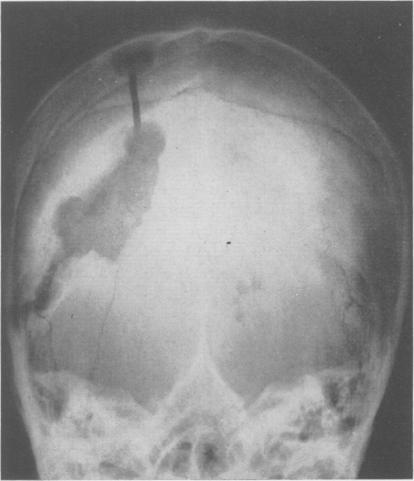

GRANT F C, AUSTIN G M

Ann Surg. 1949 Nov;130(5):963-6. doi: 10.1097/00000658-194911000-00014.